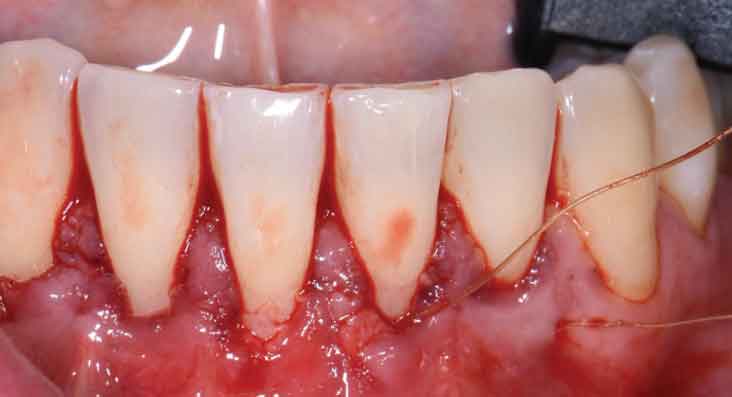

Return to "Decision-Making In Modern Mucogingival Therapy" 0521-did-mucogingival-therapy-fig-7 Next Previous